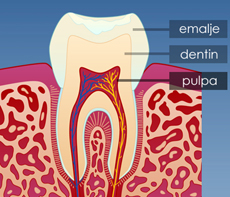

Tannens oppbygging

En tann består av flere lag. Ytterst har vi et sterkt, beskyttende lag kalt emalje. Deretter kommer et noe mykere lag kalt dentin. Lengst inne har vi nerver og blodkar, kalt pulpa.